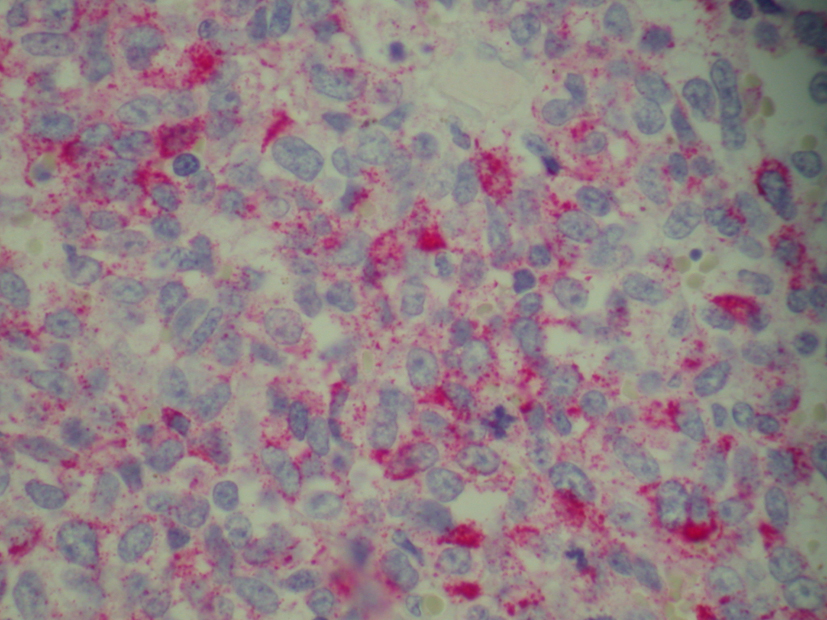

Patient was admitted for prolapsed hemorrhoids. Surgical consult was called and a CT scan of abdomen/pelvis was performed which showed colonic diverticulosis with no acute diverticulitis. The rectal mucosal appeared thickened compared with the remainder of the colon and it was advised that the possibility of a rectal or other colonic neoplasm be excluded (Fig. 1). Biopsy of the rectal mass was performed which showed malignant melanoma. Immunohistochemical stain performed showed the tumor cells to be positive for S-100, melan A and HMB-45 (Fig. 2-4) and negative for CD34, chromogranin, synaptophysin, CD20, AE1/3, CK20, CD3 and CK7. The patient was diagnosed as primary mucosal malignant melanoma. Whole body scan did not reveal any metastasis. Patient was referred to cancer center for further treatment.

![]() Click for large image | Figure 3. Biopsy of rectal mass positive for melan-A. |